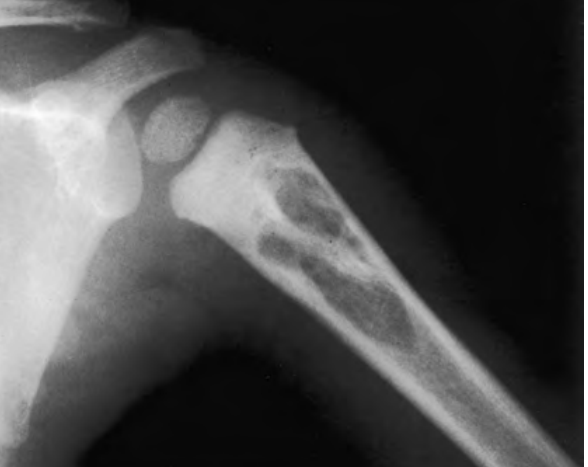

SEXO FEMININO, 32 ANOS DE IDADE, LUXAÇÃO TRAUMÁTICA DO OMBRO HÁ 1 SEMANA. QUAL O DIAGNÓSTICO?

LESÃO DE HILL-SACHS